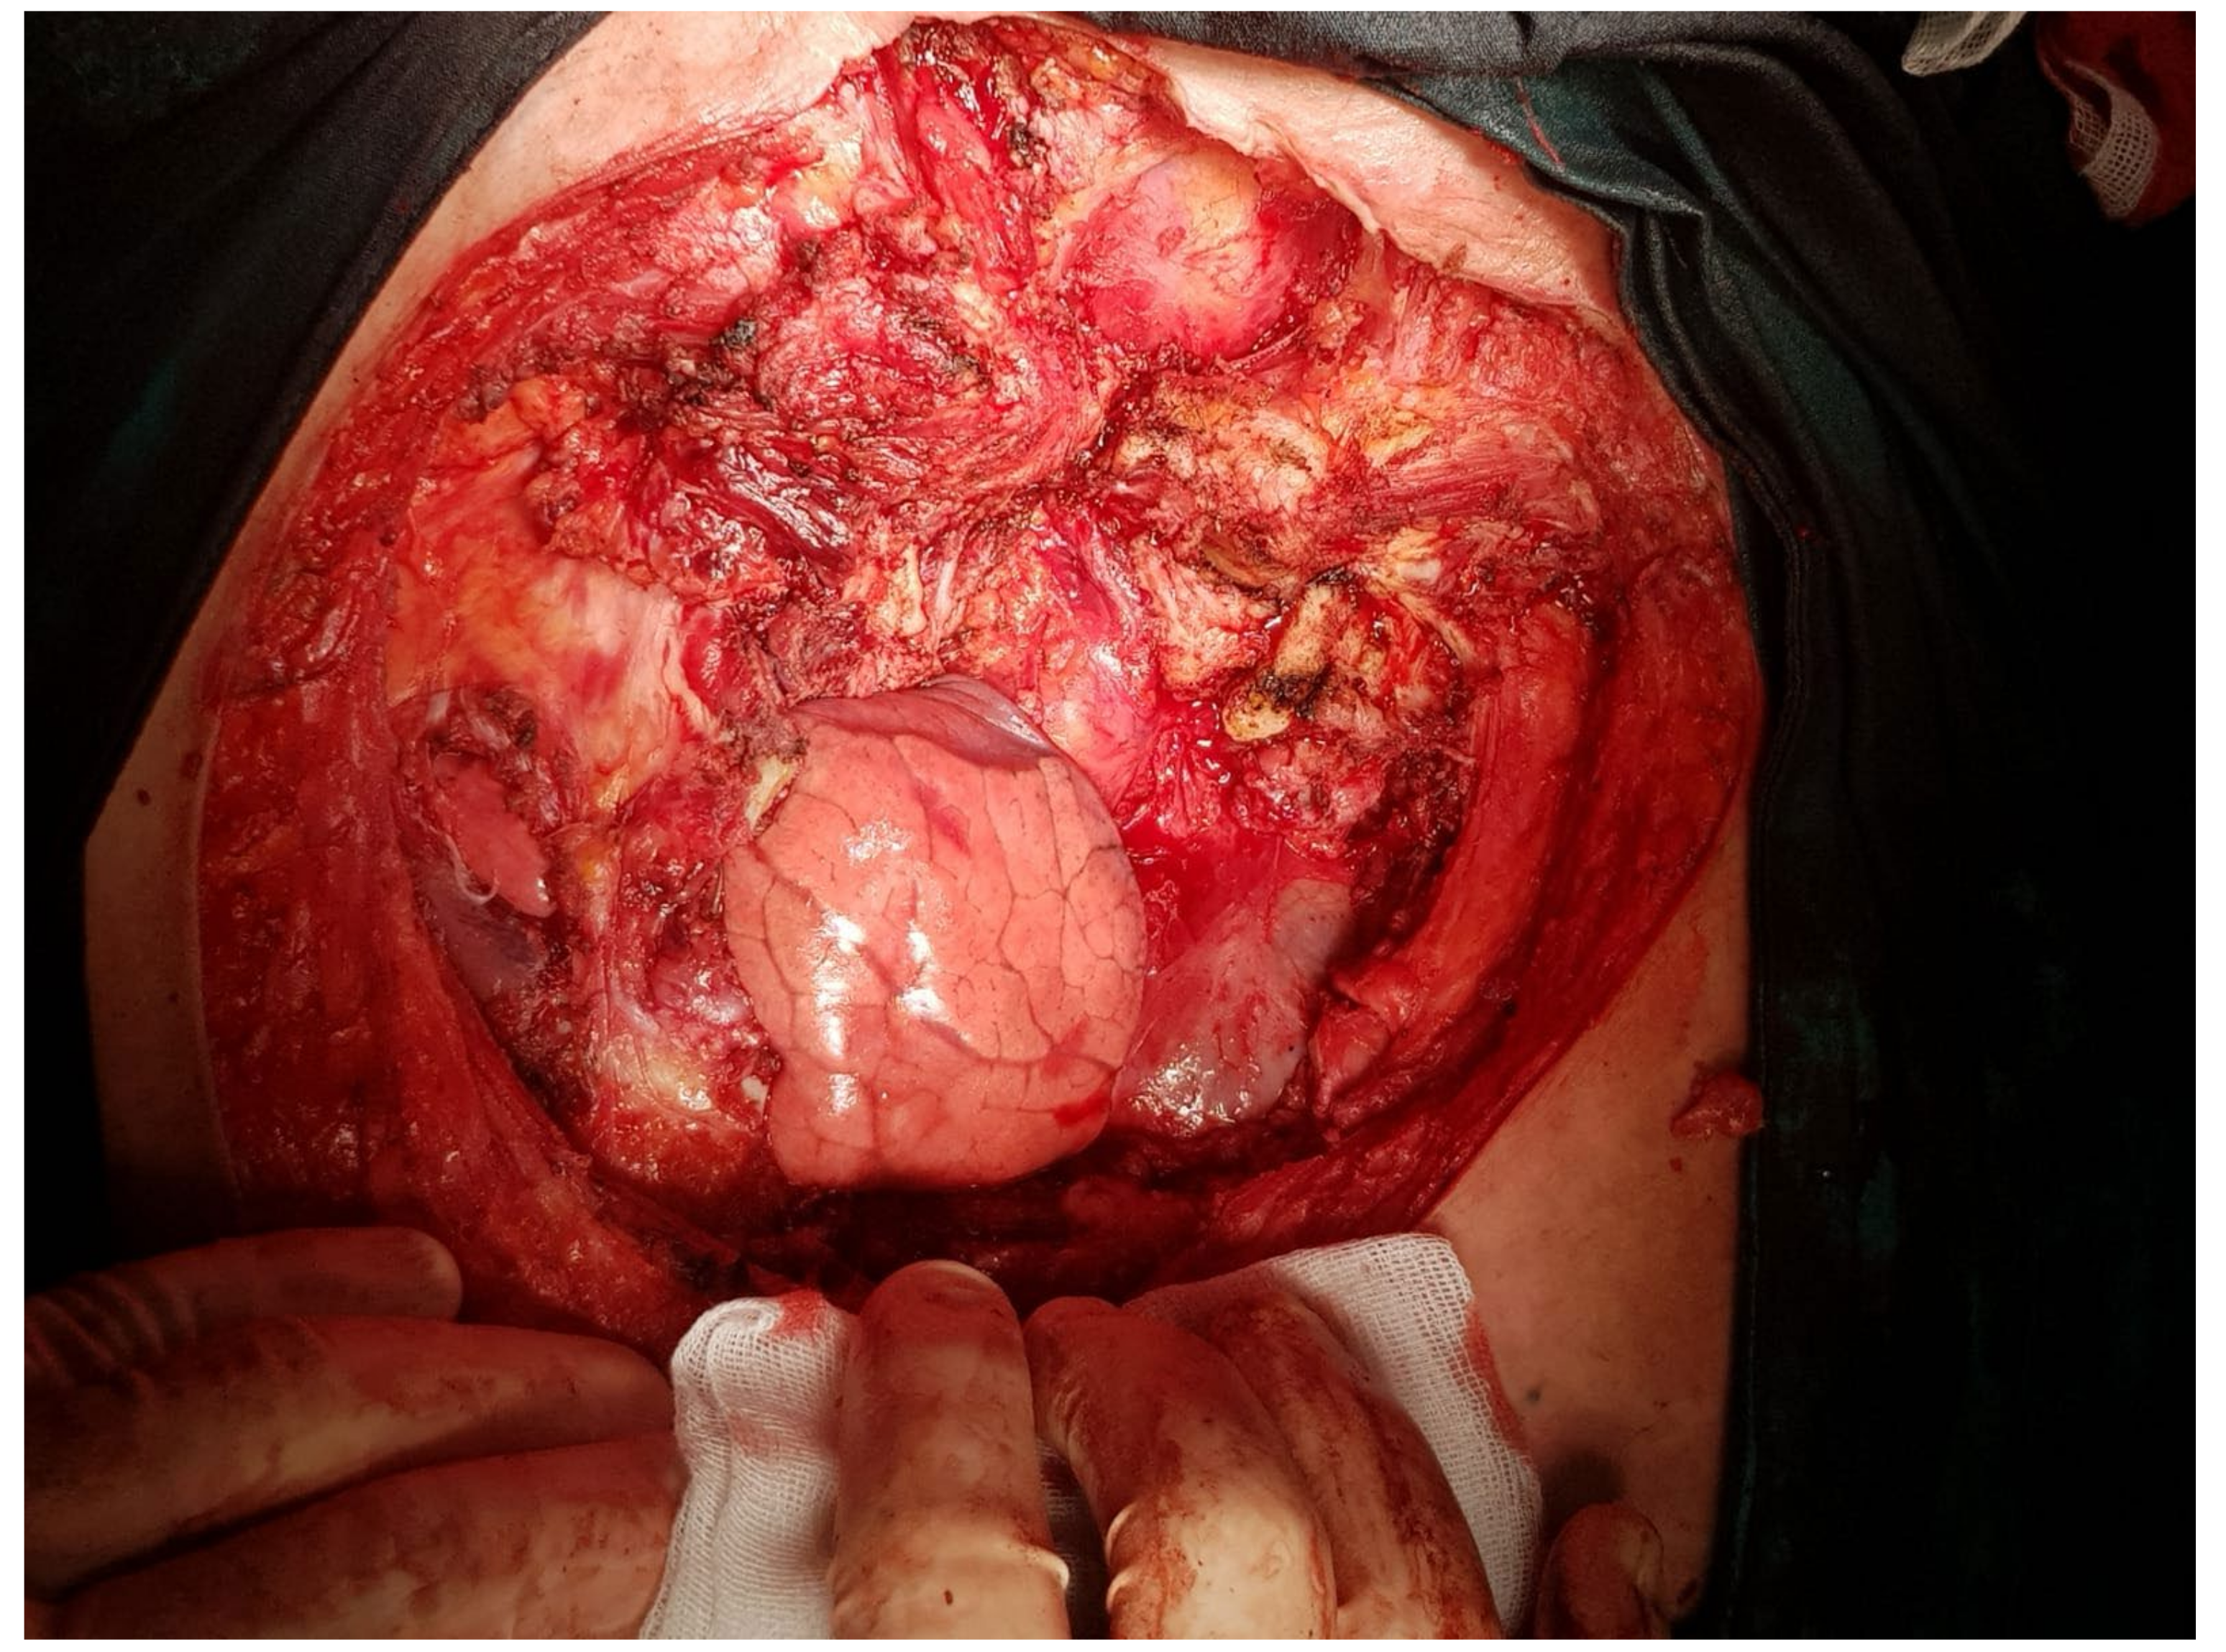

2. Case Presentation